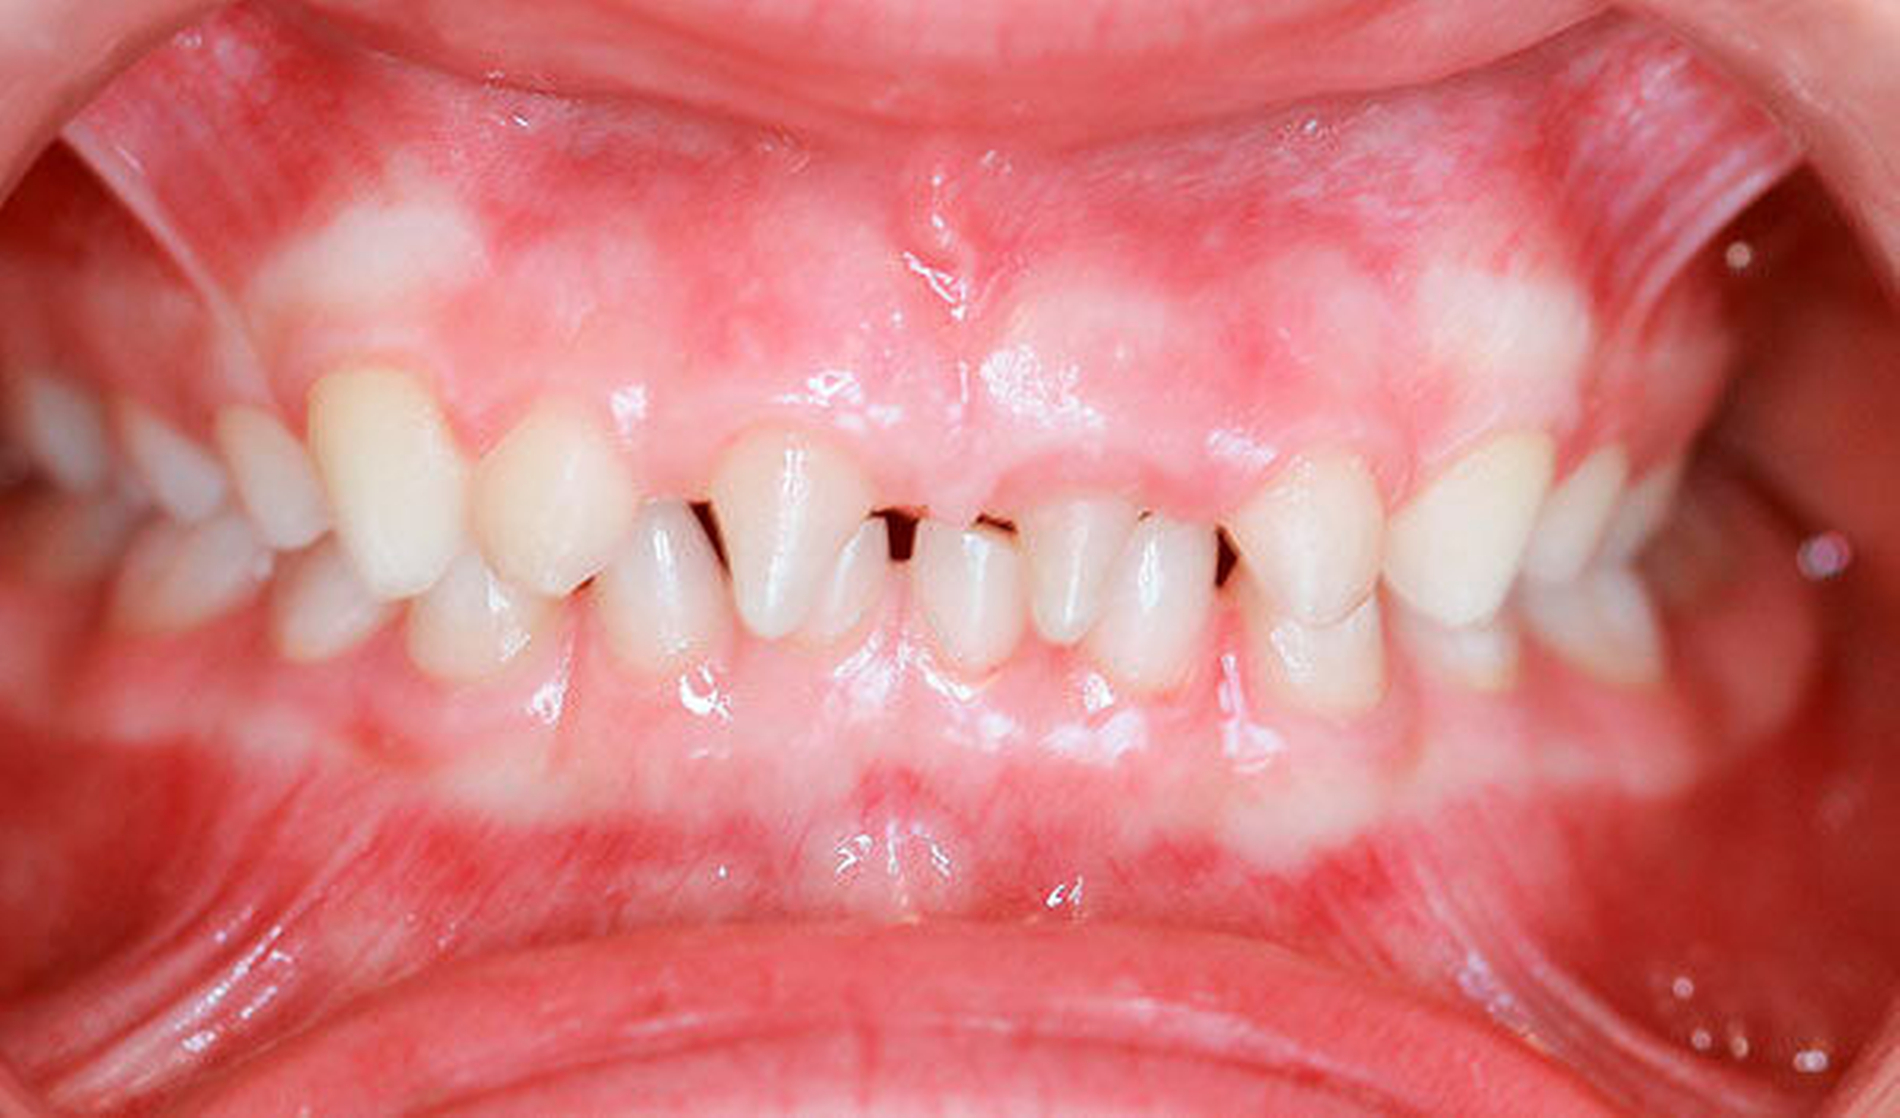

Ein siebenjähriges Mädchen wird im August 2017 aufgrund auffällig vieler Nichtanlagen in unsere Praxis für Kinder- und Jugendzahnheilkunde in Beckum überwiesen. Extraoral zeigte es keine markanten Auffälligkeiten, die Gesichtssymmetrie war weitgehend harmonisch, das Haar dunkel und dicht gewachsen. Intraoral zeigte sich ein Wechselgebiss in der ersten Phase des Zahnwechsels mit einem permanenten Zapfenzahn 11 sowie einem weiter palatinal stehenden Zapfenzahn 21 mit dem persistierenden Milchzahn 61. Die Molaren (16, 26, 36 und 46) waren in die Zahnreihen eingeordnet (Abbildungen 1 und 2). Das gesamte Gebiss war kariesfrei, die häusliche Mundhygiene gut.